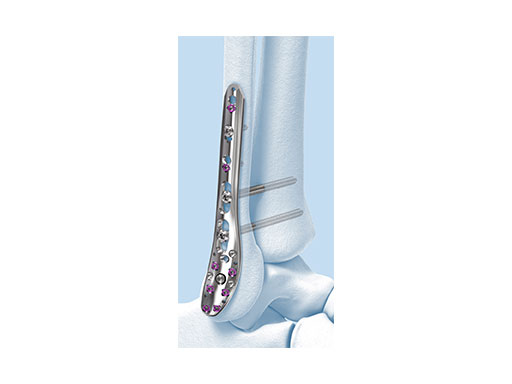

The Combi holes in the Variable Angle LCP plate shaft combine a dynamic compression unit hole with a variable angle locking screw hole. Due to the smaller sized and more numerous fixation options distally with 2.7 mm VA screws, the fixed-angle construct provides advantages for small metaphyseal segments where traditional screw fixation can be limited. The screw trajectories are optimized to support the distal articular surface. The multiple variable angle locking holes in the plate head accept 2.7 mm VA locking, 2.7 mm locking, 2.7 mm cortex, and 2.7 mm metaphyseal screws. The latter has a low profile screw head to avoid soft tissue irritations and can be used to pull the plate to the bone. Due to the numerous screw possibilities, it is important that the surgeon is familiar with which screws can be used in which plate holes. The system includes guide blocks for all plates (except T and L plates) for inserting screws in the plate head at nominal screw angles (Fig 1a-c). K-wire holes in the plate head and shaft tip accept K-wires up to 1.6 mm. They can be used to temporarily reduce articular fragments, and to confirm the location of the plate relative to the distal tibia and fibula.